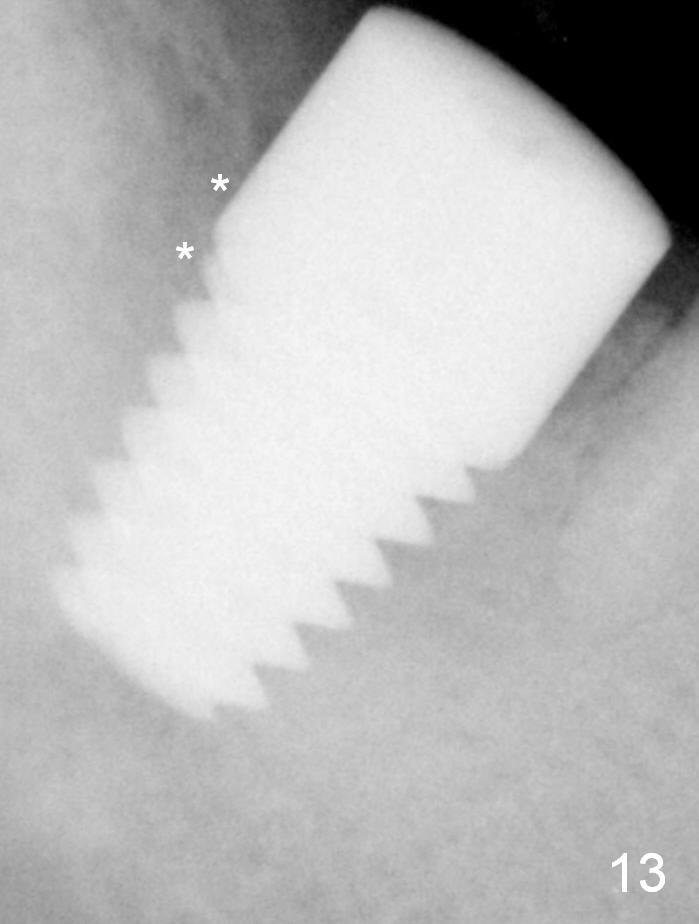

Fig.6 shows a 8x14 mm implant in place with a small gap distally (*). The distal gap has disappeared 5.5 months postop (Fig.13 *). There is no bone loss 26 months post cementation (Fig.14).